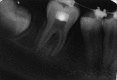

The interdisciplinary collaboration of periodontics and orthodontics has allowed teeth to be moved 2-3 times faster, reducing the time required for traditional orthodontic therapy considerably. Periodontally accelerated osteogenic orthodontics (PAOO), also known as Wilckodontics, is a combination of a selective decortication facilitated orthodontics and alveolar augmentation. With this technique, there is no dependence on the pre-existing alveolar volume. This case report describes the treatment of permanent mandibular molar protraction in a 14-year-old patient undergoing orthodontic therapy using PAOO with piezosurgery.